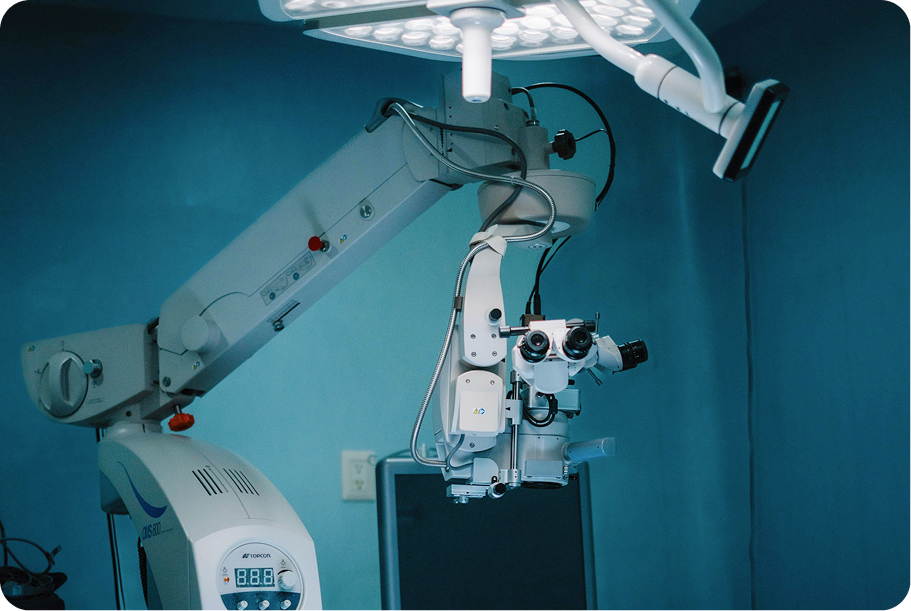

Providence implemented an AI-enabled automation suite to streamline Radiation Oncology treatment planning, replacing slow, manual contouring and plan-review steps with high-accuracy, automated workflows.

This helped alleviate burnout and admin burden by enabling access to auto contouring tools, reduced data access and review time for radiologists, reducing variability and rework.